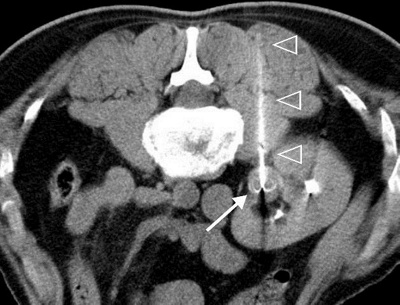

Bei kleineren Tumoren, d.h. wenn der Nierentumor kleiner 4 cm im Durchmesser ist, kommt auch eine minimalinvasive Behandlung infrage. Dieses Verfahren nennt sich Thermoablation, bei der Tumorzellen durch Hitze zerstört werden. Die Hitze wird dabei über eine spezielle Sonde erzeugt, welche in Lokalanästhesie CT-gestützt in den Tumor eingeführt wird. Vergleichende Langzeitstudien zeigten keine Überlebensvorteile der operierten gegenüber den minimalinvasiv behandelten Patienten.